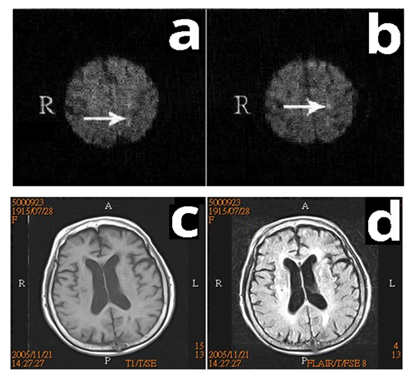

A 90‒year‒old, right‒handed female visited the gastrointestinal (GI) department of our hospital on October 28, 2005 with complaints of poor appetite and low grade fever. The patient was admitted to the GI ward under the impressions of ileus and pyuria. On November 18, 2005, the patient developed poor muscle power, right hemiplegia, and disturbed consciousness. Magnetic resonance imaging (MRI) of the brain revealed acute left side cerebral infarction Figure 1(A‒B) and an old lacunar infarction on the right side Figure 1(C‒D) Inpatient rehabilitation was arranged for neurological recovery. On December 21, 2005, the patient's caregiver noted prominent involuntary movement around the mouth similar to a rabbit's behavior. Upon inquiry, the patient revealed no previous psychiatric history and had never taken antipsychotic medication. On examination, a rhythmic lip‒oral movement was observed, and the frequency was measured to be 4 to 5Hz. However, the frequency of movement increased when she was stressed or distracted and decreased during voluntary activities such as talking. There was no involvement of the tongue, and lip‒oral movements were absent during the patient's sleep. We observed no abnormal movements anywhere else on the body. Based on these symptoms, a diagnosis of rabbit syndrome was made. An MRI study (on November 21) of the patient's brain produced unremarkable findings aside from the previous lesions. To further investigate the syndrome, the regional cerebral perfusion scan with an ethyl cysteinate dimer (ECD) single photon emission computed tomography (SPECT) SPECT scan of the patient's brain was performed, which revealed increased perfusion of the right basal ganglia and left thalamus Figure 1A & Figure 2A. The patient was prescribed the antiparkinsonian medication Madopar (levodopa/benserazide), 250mg bid (January 2‒9). After 7 days, the abnormal oral motions faded outré solved, the hemiplegia was mildly improved, and the other symptoms resolved resolved. Upon fade‒outre solution of the patient's symptoms after 7days, Madopar was discontinued, and one week later (January 23) we repeated the SPECT scan to reevaluate perfusion of the basal ganglia. Findings from the SPECT scan indicated that basal ganglia perfusion had returned to normal. Furthermore, the scans indicated decreased uptake in the left thalamus Figure 1F & Figure 2B. Once the patient exhibited relative recovery of muscle strength of her right limbs, she was discharged on January 23, 2006.

Figure 1 In our a 90‒year‒old female patient, brain magnetic resonance imaging showed 2‒3multiple small acute infarctions in the left frontoparietal lobes in DWI (A‒B), old infarctionts in the left paracentral gyri (not shown) and right periventricular white matter in T1‒weighted images (A‒C) and FLAIR images (C‒D). No obvious lesions were found in the basal ganglion or thalamus.